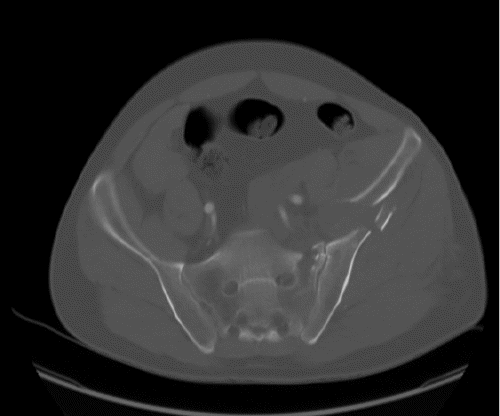

The patient's condition stabilized, and the pain was controlled with analgesia. CT showed no brain injury, but there were multiple left-sided comminuted rib fractures with displacement along the posterior and lateral aspects. In addition, it revealed the presence of hydropneumothorax; lung contusion with thoracic wall subcutaneous emphysema; right-sided mild pneumothorax; undisplaced fracture of the sternal body; herniation of the stomach into the pericardial cavity (Figure 1); no intraabdominal fluid or air and no solid organs injury; fracture of the transverse processes of the L3/L4 and L5 vertebrae; fractures of the left glenoid bone and left pelvic bone; multiple comminuted displaced fractures involving the iliac, acetabular, and pubic bones, with the displacement of the iliac bone fractures; right inferior pubic ramus nondisplaced fractures; and fracture of the left sacral alar and proximal left sacral segments (Figure 2).

Figure 2. Bone CT of Pelvic Fracture. A) Axial, B) Sagittal, and C and D) Coronal Views. Published with Permission

A) Axial View

B) Sagittal View